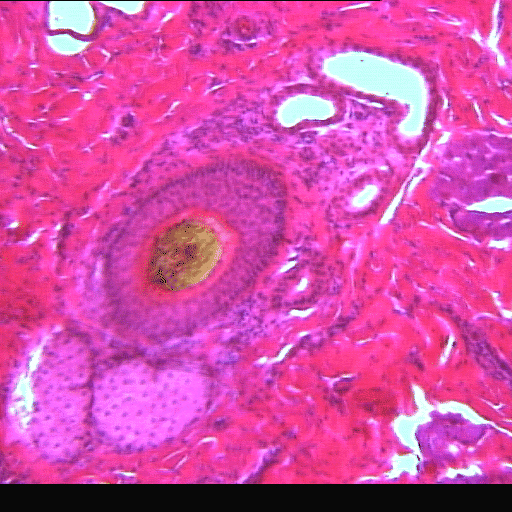

(EN) : Cross section of hedgehog thymus (Hematoxylin and eosin stain (H&E), x40, Slide RCB-5 I7.6): Possibly blood vessels?

(FR) : Coupe transversale du thymus de l'hérisson (coloration à l'hématoxyline et à l'éosine (H&E), x40, Lame RBC-5 I7.6): Peut-être des vaisseaux sanguins ?